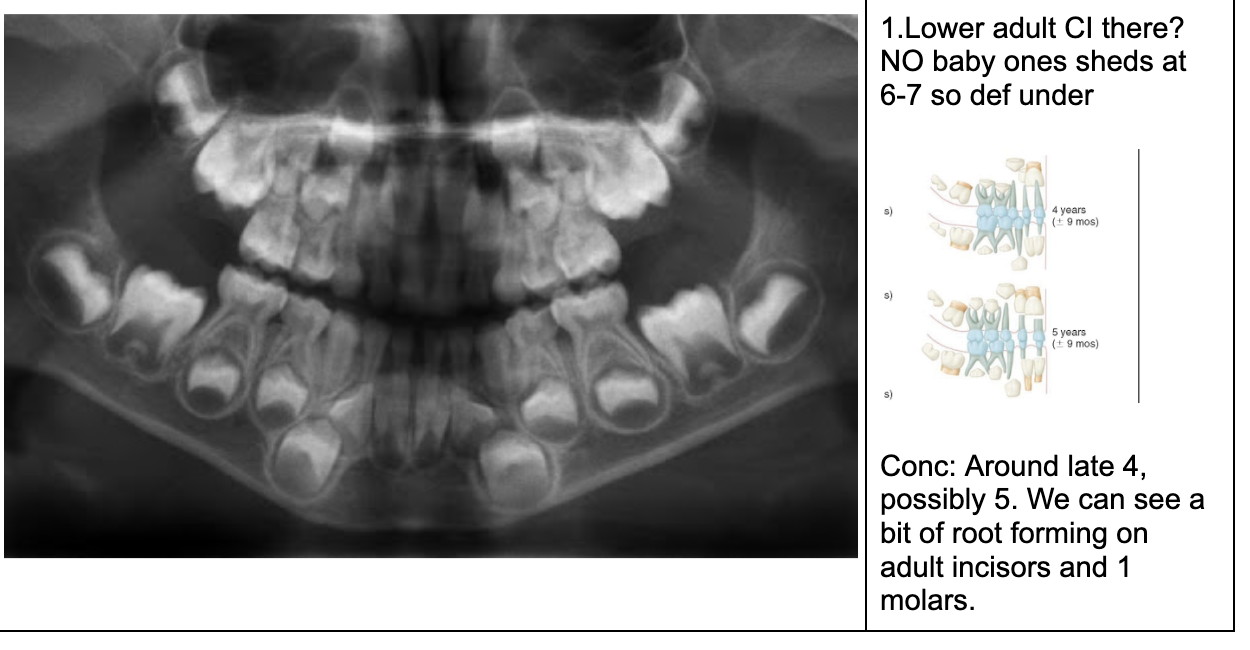

1.Ad. LOWER central incisors present? Yes. definitely 6-7 or older

1. Ad. UPPER CI present? Yes def. 7-8 y.o

3.Ad. Upper LAT incisor present (baby sheds 7-8)? NO so still under 7-8

Conc: pt is under 7